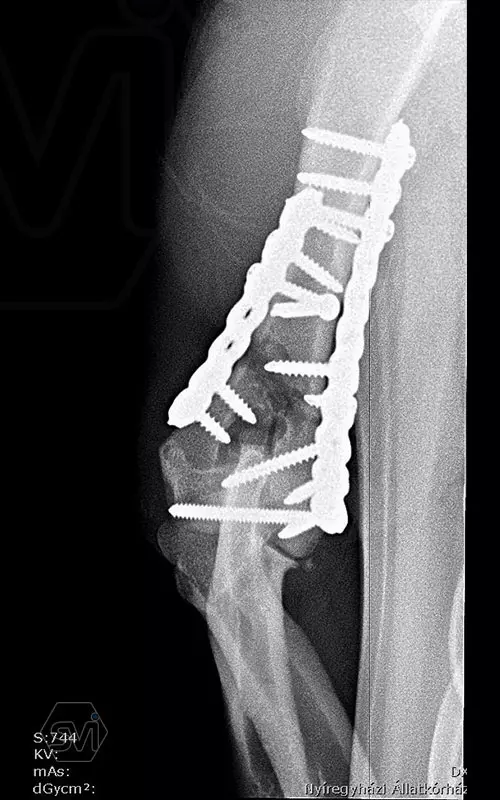

In our first case, we got right to the heart of it: we operated on a 2-year-old dachshund-type mixed dog weighing 9 kg, who overstretched his right humerus while stepping on pallets and suffered a Y-shaped humerus fracture that extended into the elbow joint combined with a large longitudinal splinter. To treat the fracture, we chose the new, cutable poliaxial locking plate, and immediately placed two, one medially and one caudolaterally. The intercondylar fracture and the longitudinal diaphysis fragment were each fixed with a 2.4 lag screw.

The ability to transition between sizes (2.0-2.4) was very useful. We positioned the plate with thinner (2.0 mm) cortical screws, the fragments were fitted to each other, and after the final state was established, we further stabilized the system with the locking screws placed in the empty holes, and then the thinner cortical screws were also replaced with thicker locking ones.

The plate behaved very well, it was much easier to work with than the straight plates used so far, it was easy to cut to size and shape it on the curved dachshund bone.

The advantage of polyaxiality proved to be particularly useful here, where it is very easy to drive the screw into the joint! There is no need to talk about the advantages of lockig systems around the elbows, where the pulling and stretching forces are magnified.

TIP: On the medial side, the very short screw above the fracture line was only used as a "blind plug" so that the hole would not remain without a screw, and the plate would not have a weak point above the fracture.More information: